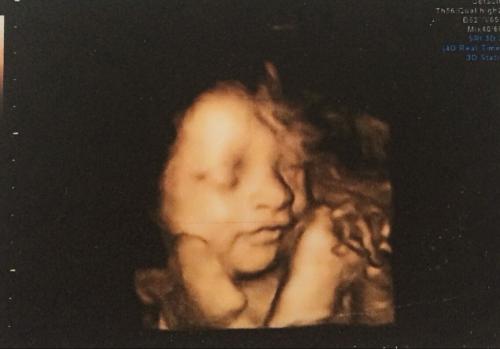

3,四维又是在三维的基础上又增加了一个空间轴,形成了动态的立体图像。

二维是普通B超,图像呈黑白两色。三维、四维呈土黄色,很多人以为彩超彩超肯定是彩色的,其实并不是,之所以称为彩超只是因为会用彩色标注心脏、血流等指标。

二维观察到的只是平面图像,三维观察到的则是静态的立体影像,而四维就厉害了,能观察到动态的立体影像。

而且三维比之二维更加全面,清晰。四维比之三维又更多方位,更多角度,能实时地观察胎儿的动态立体结构。